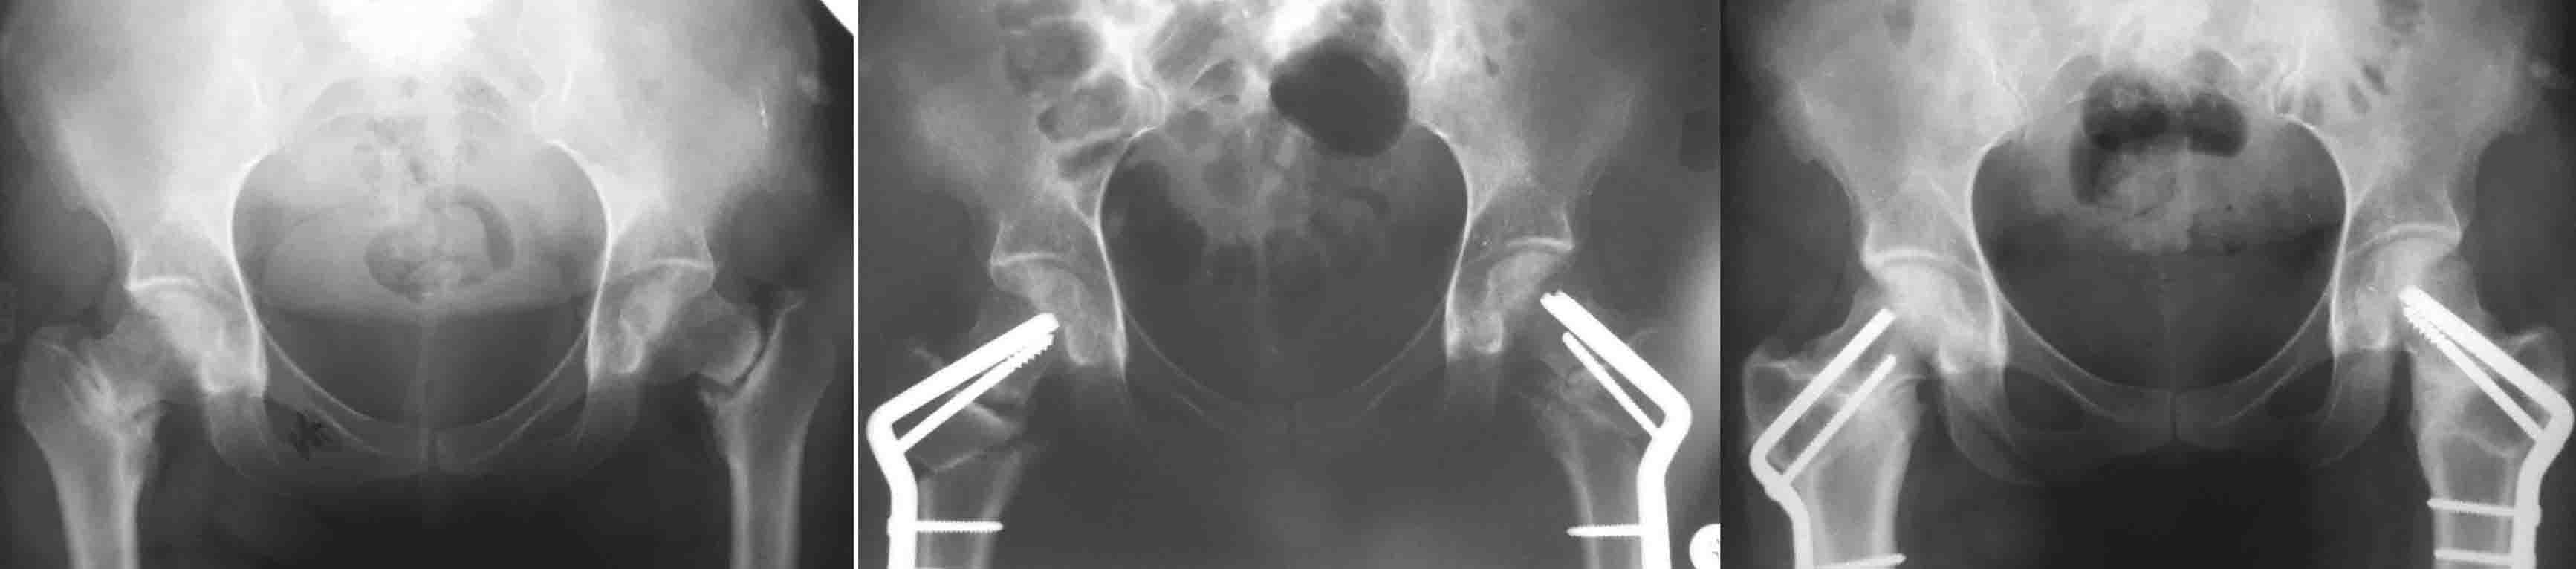

И клинковые и DHS, это всего лишь способ остеосинтеза, хотя, наверное, клинковые  дают большую ротационную стабильность (по оси шейки), менее травматичны. Но это не постулат ( 1943 J Bone Joint Surg Am.;25:319-339. W. P. Blount BLADE-PLATE INTERNAL FIXATION FOR HIGH FEMORAL OSTEOTUMIES). При подвертельных остеотомиях с латерализацией клинковые пластины метод выбора (по другому латерализацию дистального не выполнишь). Оптимальними являються рассчеты СORA  по Dror Paley (centr rotation and angulation). Взяты из книги Principles of Deformity Correction by Dror Paley. Для примера  межвертельные при двусторонних ложных  cуставах шеек.